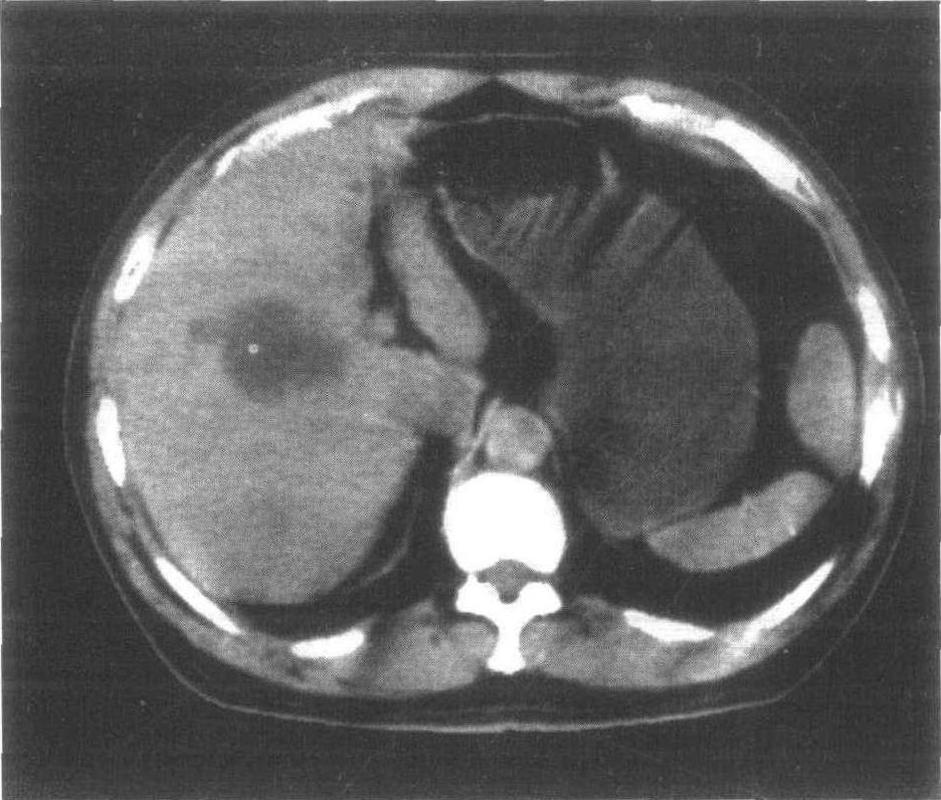

肝囊肿ct图片报告,肝囊肿ct图片

肝囊肿-腹部ct诊断-医学

肝囊肿ct图片

肝囊肿ct图片影像

肝囊肿ct图片怎么看

多发性肝囊肿ct图片

肝囊肿ct